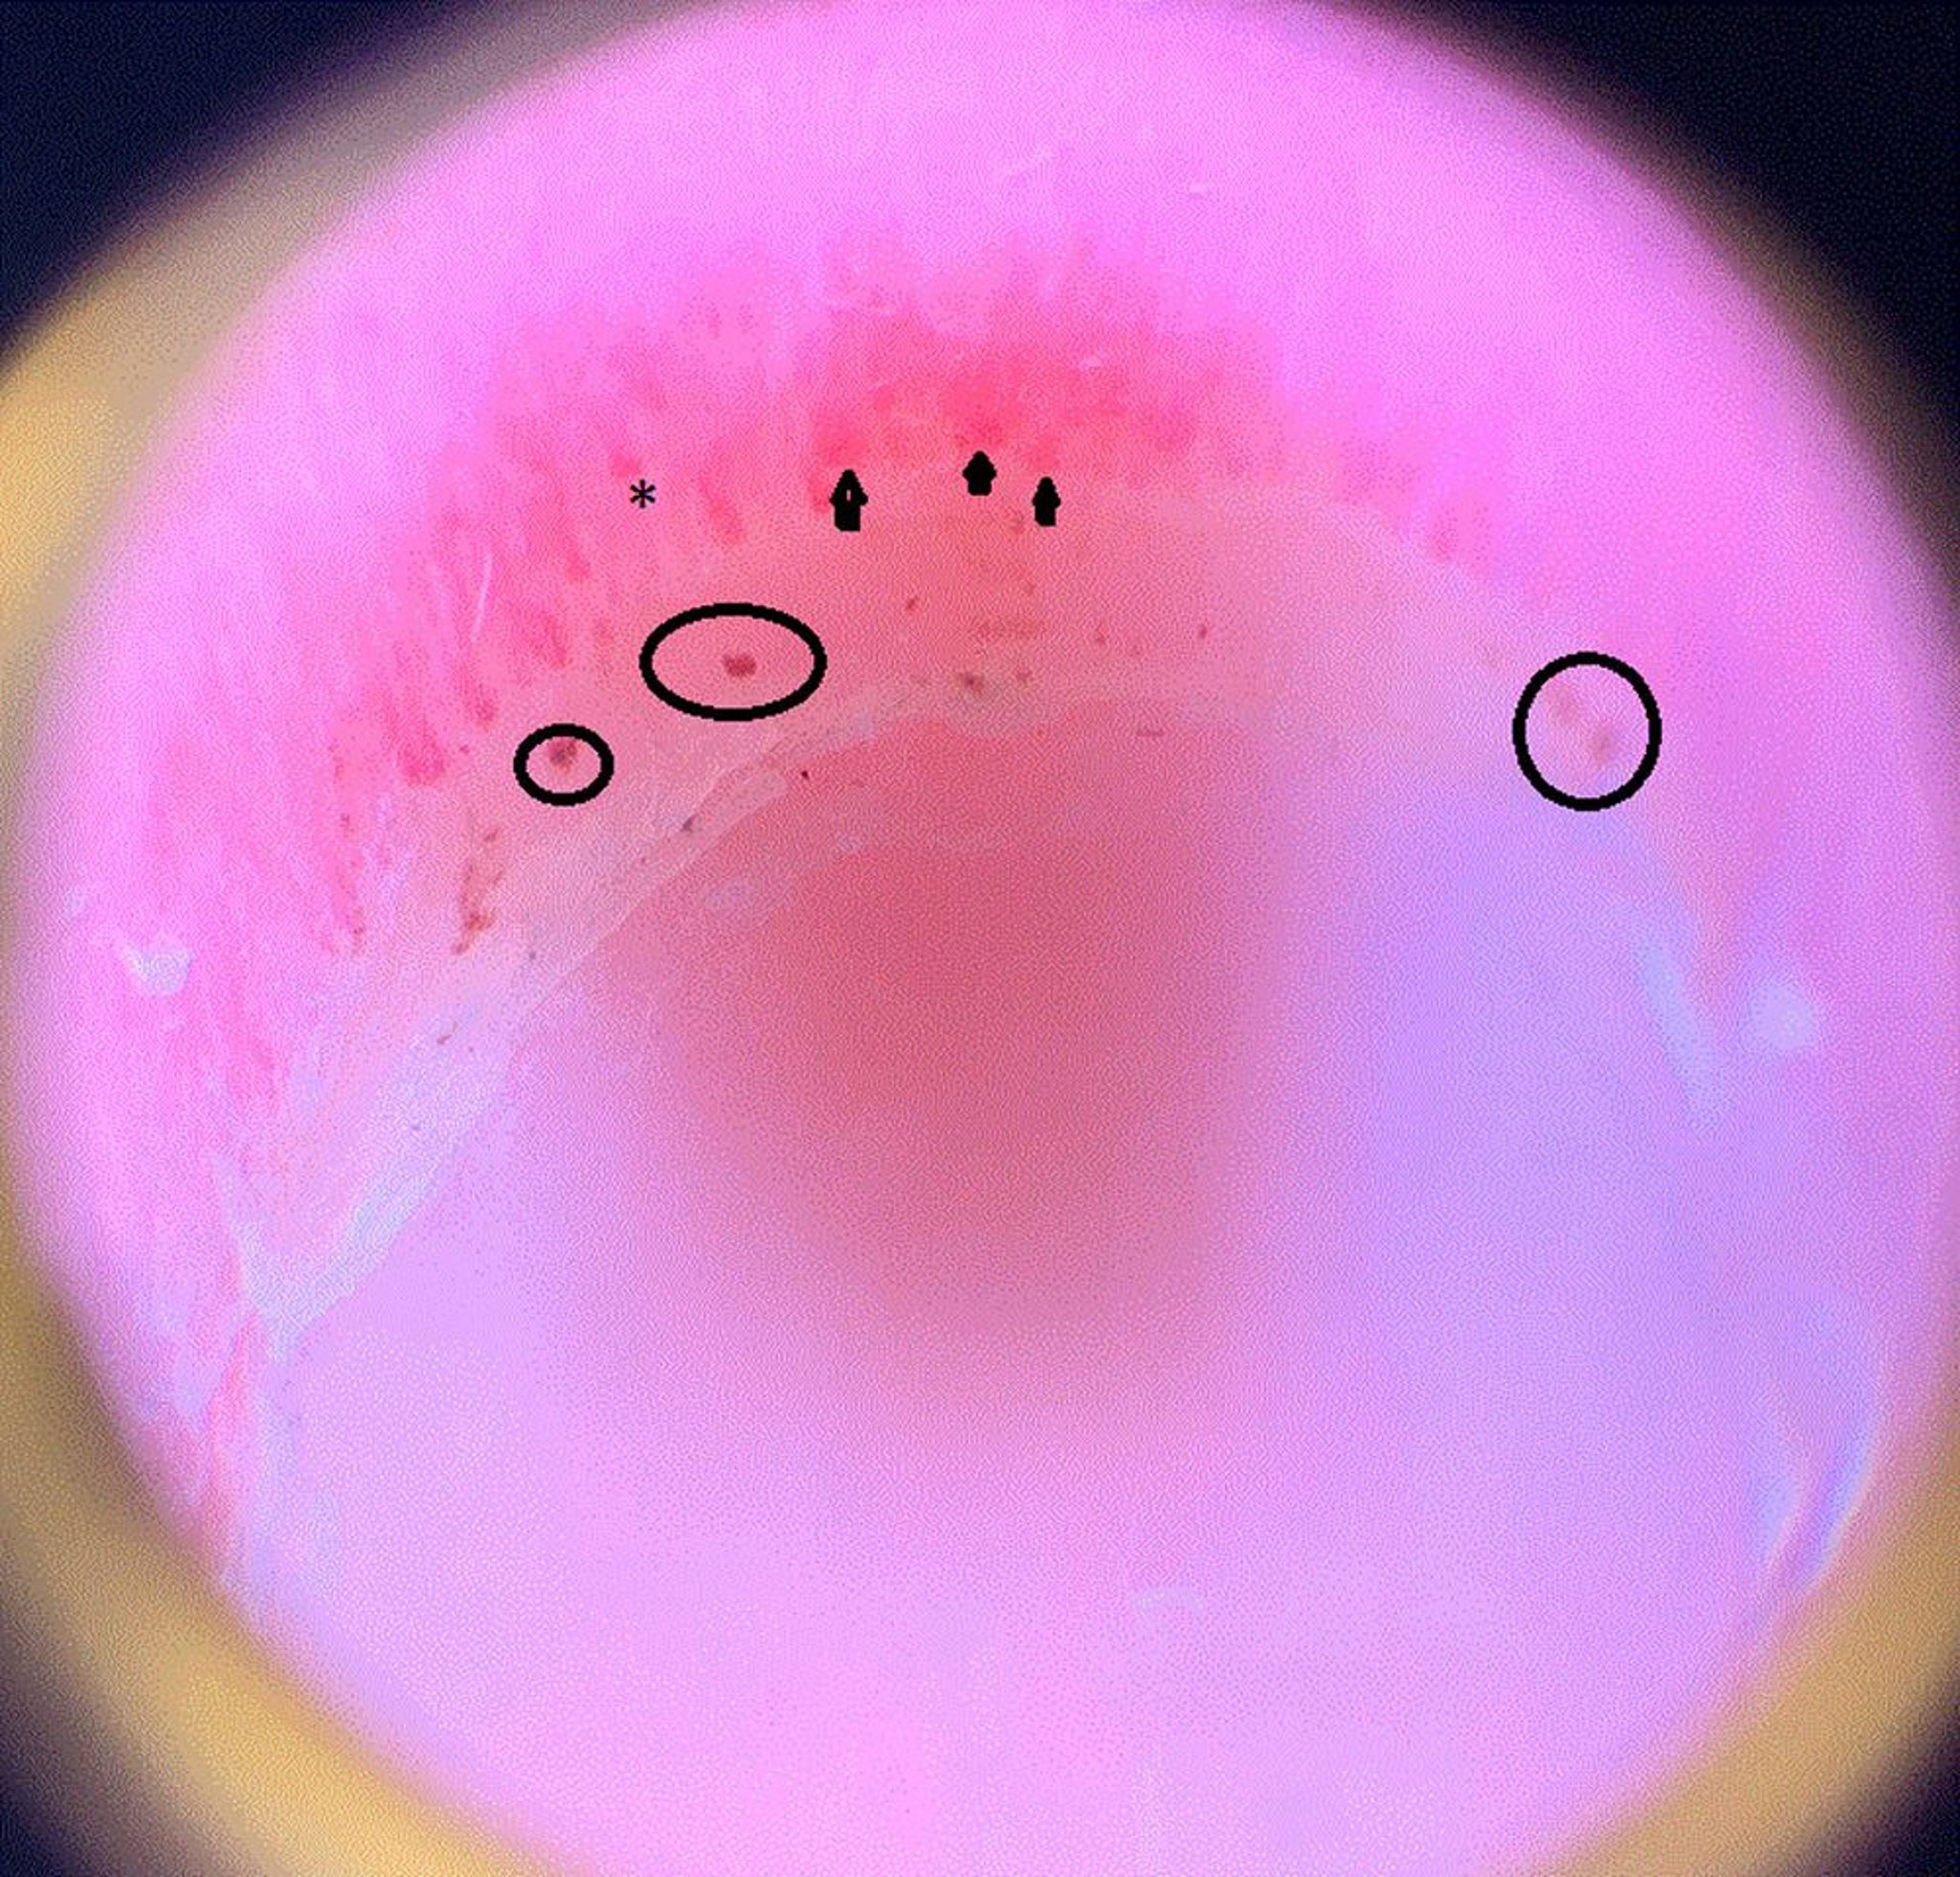

Esta imagem mostra alças capilares dilatadas (setas); uma área de oclusão capilar, o que significa que a extremidade do capilar termina prematuramente e desaparece (asterisco); e hemorragias periungueais (círculos) na prega ungueal de um paciente com esclerose sistêmica.

Imagem cedida por cortesia de Sanjeev Patil, MD.